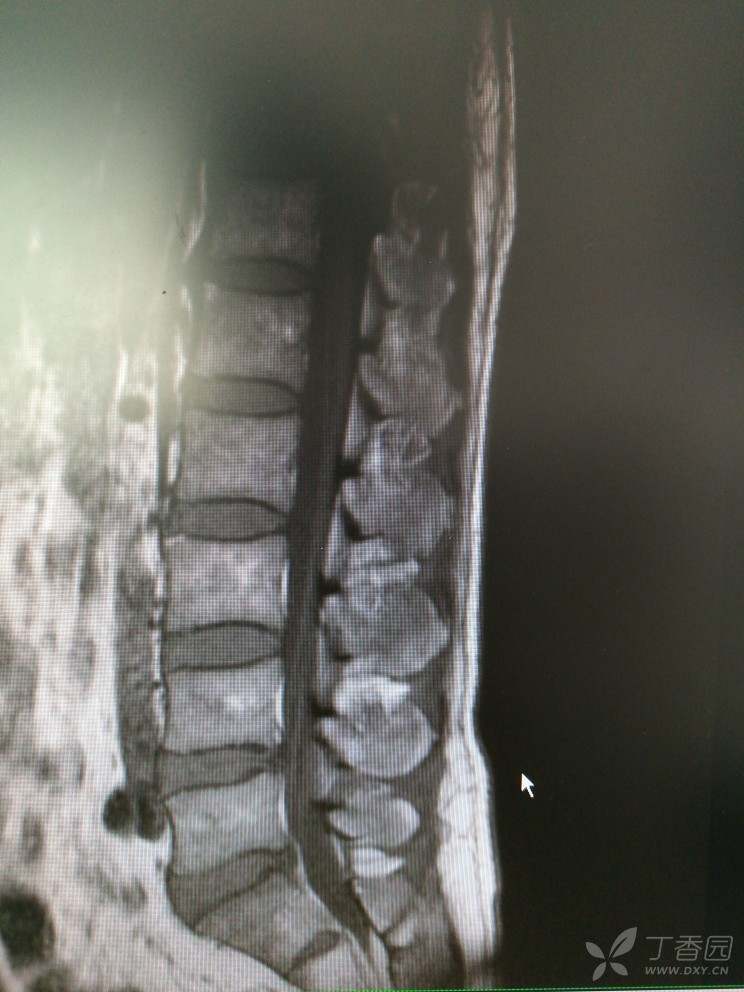

双下肢麻木查因

患者男,46岁,双下肢麻木2年余。

2年前无明显诱因出现双下肢麻木,双下肢沉重感,感觉对称,在坐位、平卧位时发生,活动或抬高下肢后缓解,无双下肢放射痛及乏力等。

查体:腰椎活动可,腰肌稍紧,L2-S1椎无明显压痛,双侧坐骨行程无压痛,直腿抬高试验(-),加强试验(-)肌力5级,肌张力正常,生理反射存在,病理反射未引出。

入院查MRI

我想问还是考虑L4/5 L5/S1椎间盘的变性引起的吗?